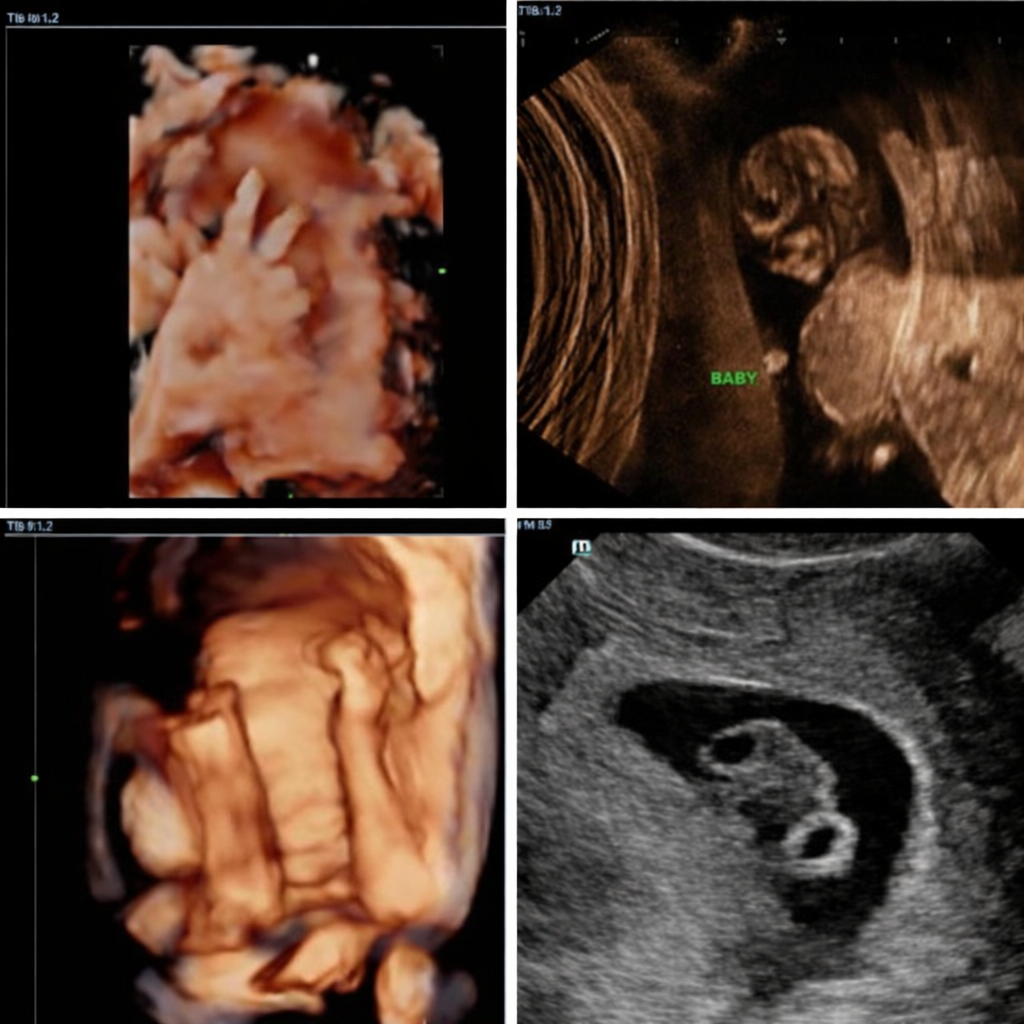

3D ultrasound scan: A Deeper Glimpse

Now, if we discuss a 3D ultrasound scan, unlike 2D, which shows internal organs and structures, 3D technology captures still, three-dimensional images of your baby. Imagine seeing your baby’s adorable nose, tiny fingers, or even a cute yawn! This technology compiles multiple 2D images from different angles to create a lifelike, static picture. It’s a wonderful way to visualize your baby’s features and truly get that “first portrait” moment. For expectant parents, seeing these detailed images often makes the pregnancy feel even more real and personal.

4D ultrasound scan: Bringing Movement to Life

If a 3D scan is a still photo, a 4D scan is a whole live video! The “4D” stands for “fourth dimension,” which is time. You may see your baby smiling, yawning, hiccuping, stretching, and moving hands and feet. It’s an incredibly dynamic and moving experience that offers an unparalleled bonding opportunity for you, your partner, and even excited siblings or grandparents. Imagine watching your baby’s expressions unfold right before your eyes!

HD Live (5D) Scan: Unparalleled Clarity

HD Live, often known as 5D scanning, brings an almost magical touch to pregnancy imaging, turning ordinary ultrasounds into beautifully lifelike moments. With advanced lighting and shadowing, it creates soft, detailed images that resemble your baby’s first photograph—complete with tiny expressions and delicate features. Many parents are amazed to see their baby smile, yawn, or gently move, making the experience deeply emotional and unforgettable. It’s more than just a scan; it’s a chance to connect, imagine, and fall in love even before birth, capturing memories that families often cherish long after the pregnancy journey ends.